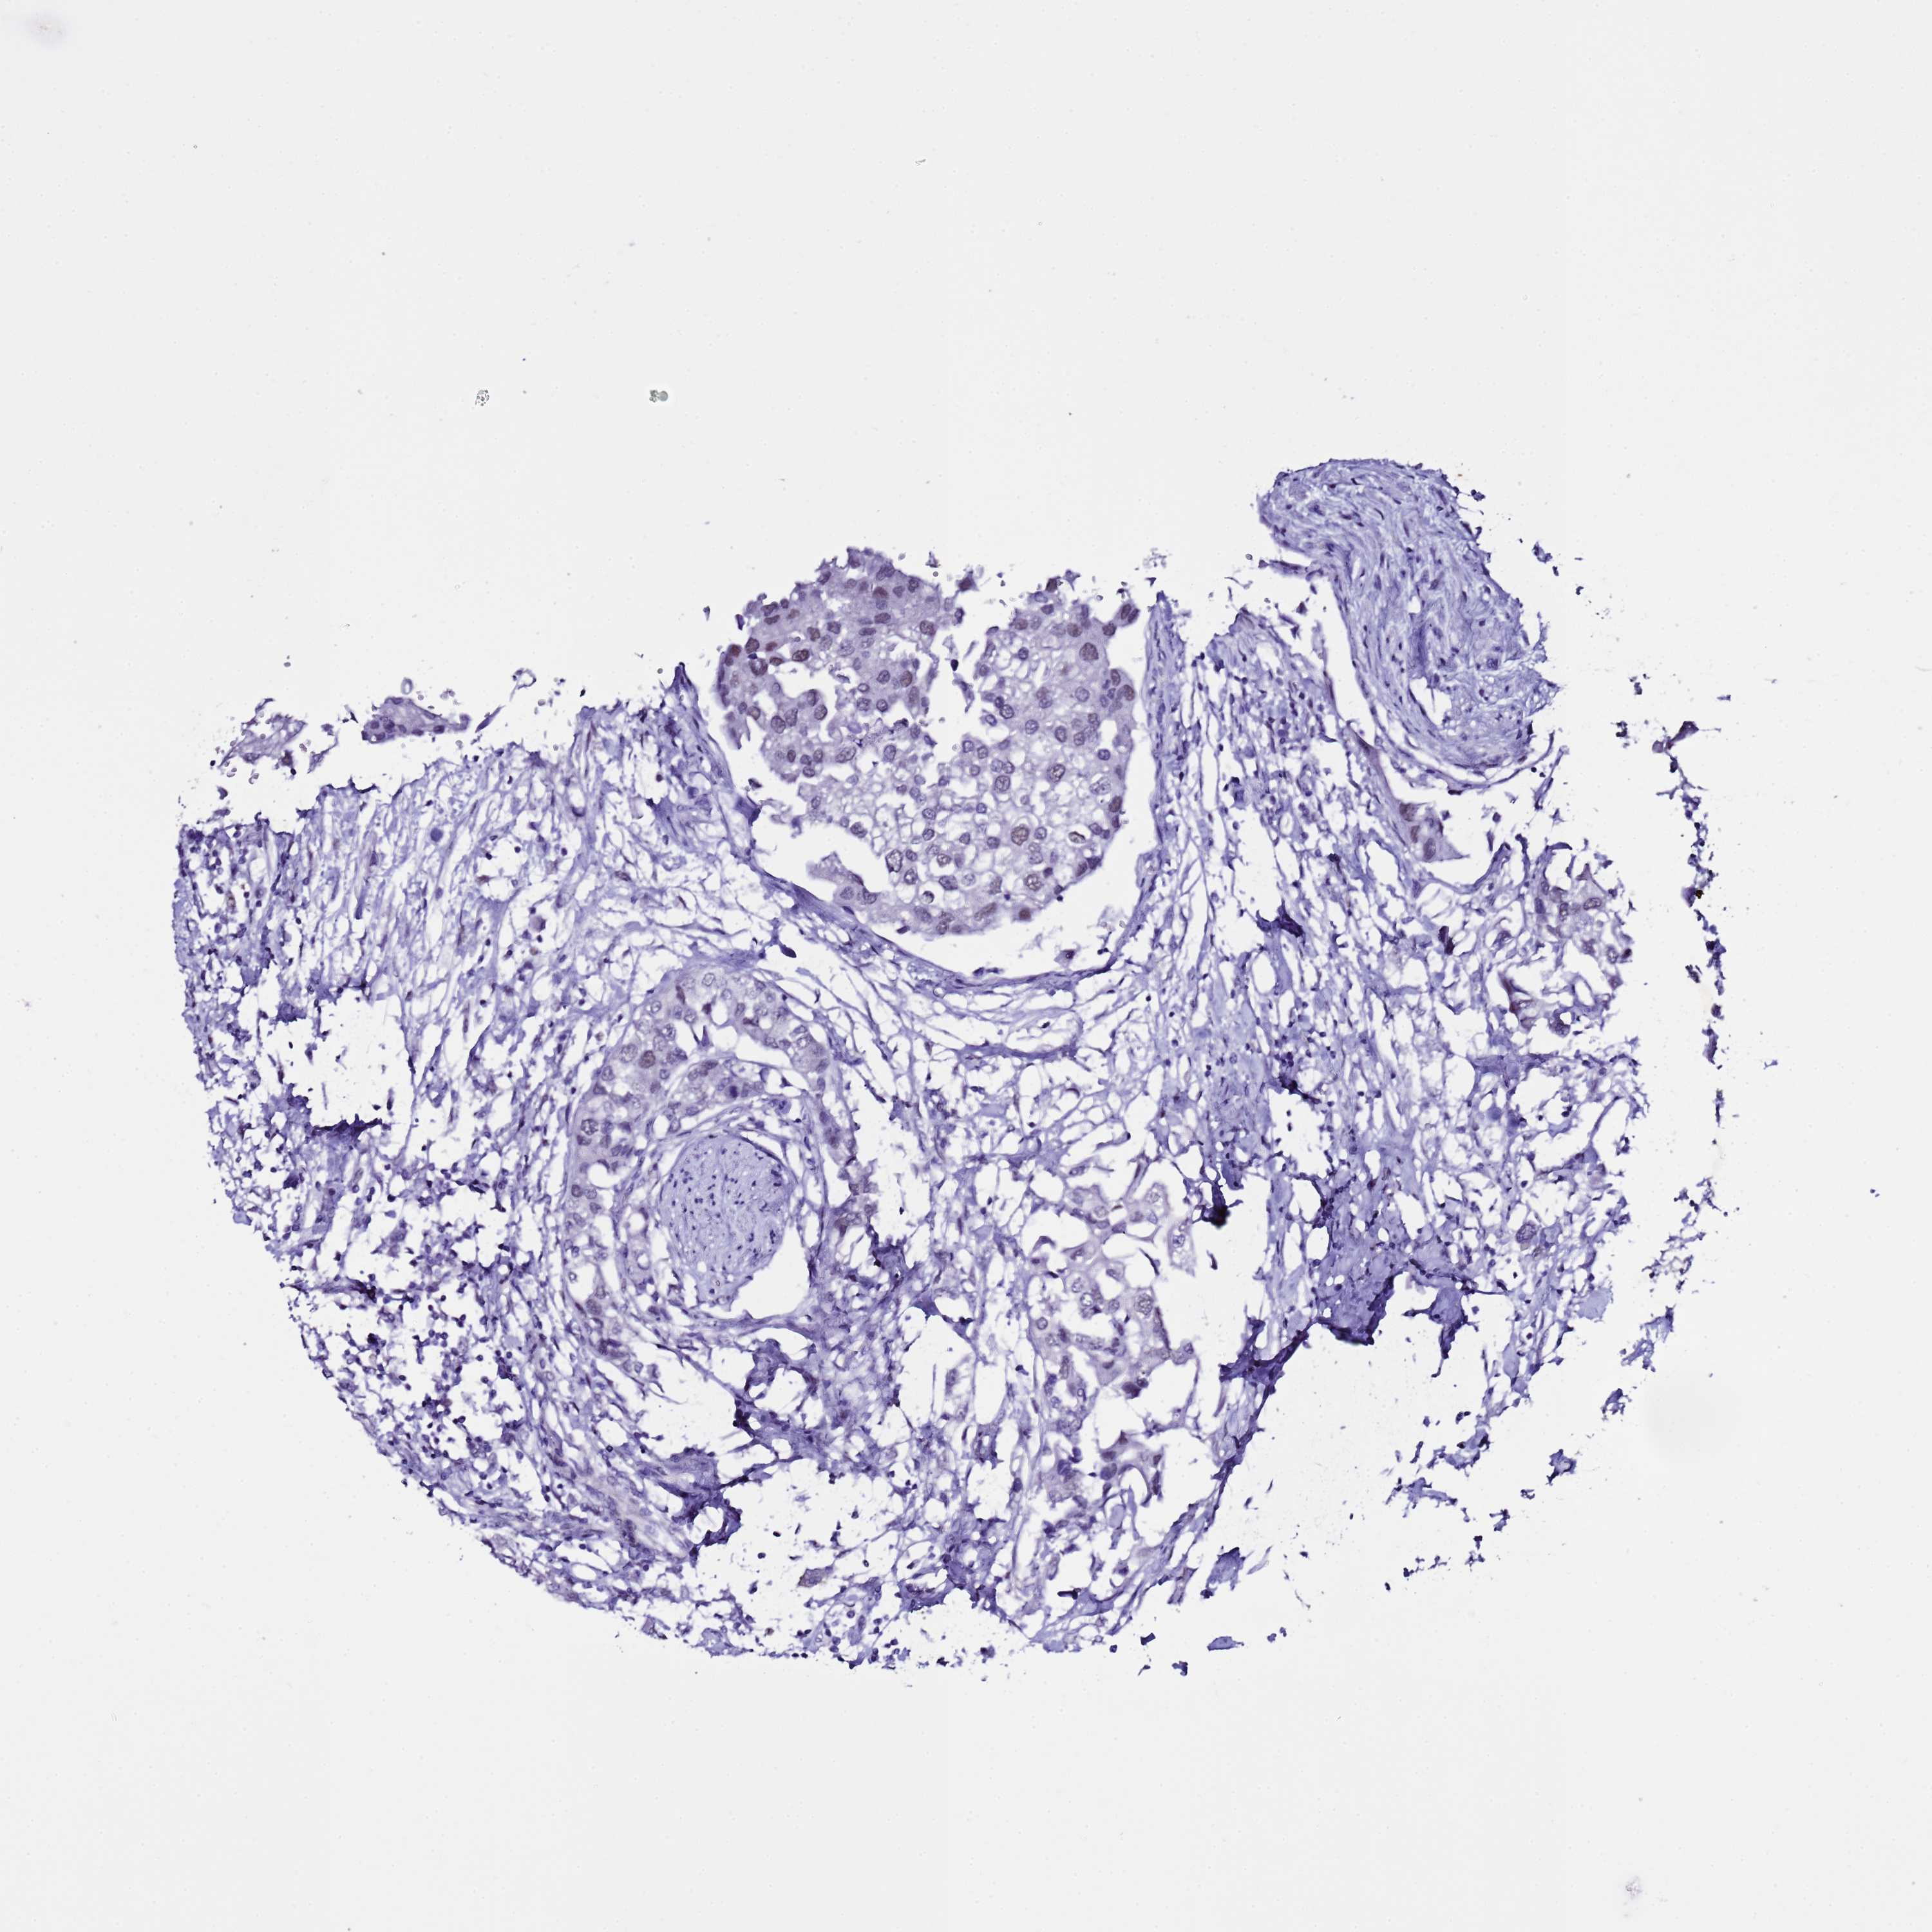

UROTHELIAL CANCER - Protein expressioni

A mouse-over function shows sample information and annotation data. Click on an image to view it in a full screen mode. Samples can be filtered based on level of antibody staining by selecting one or several of the following categories: high, medium, low and not detected. The assay and annotation is described here.

Note that samples used for immunohistochemistry by the Human Protein Atlas do not correspond to samples in the TCGA dataset.

Antibody stainingi

Antibody staining in the annotated cell types in the current human tissue is reported as not detected, low, medium, or high, based on conventional immunohistochemistry profiling in selected tissues. This score is based on the combination of the staining intensity and fraction of stained cells.

Each image is clickable and will lead to virtual microscopy that enables deeper exploration of all samples and also displays staining intensity scores, fraction scores and subcellular localization as well as patient and tissue information for each sample.

Antibody HPA019762

Staining

High

Medium

Low

Not detected

Intensity

Strong

Moderate

Weak

Negative

Quantity

>75%

75%-25%

<25%

None

Location

Urothelial carcinoma, High grade

Urothelial carcinoma, Low grade

Urothelial carcinoma, NOS